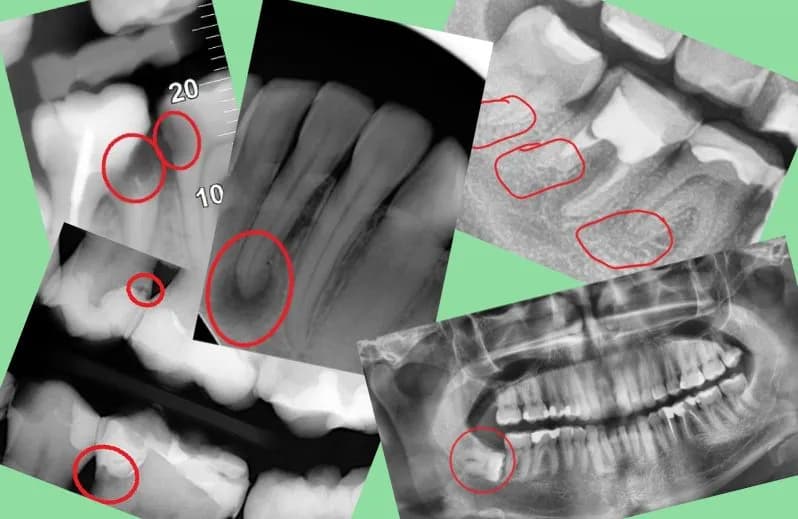

Skutki uboczne leczenia kanałowego zęba: ból, obrzęk i powikłania

Poznaj najważniejsze skutki uboczne leczenia kanałowego zęba, takie jak ból, obrzęk i powikłania. Dowiedz się, jak zapewnić skuteczną regenerację zęba po leczeniu.